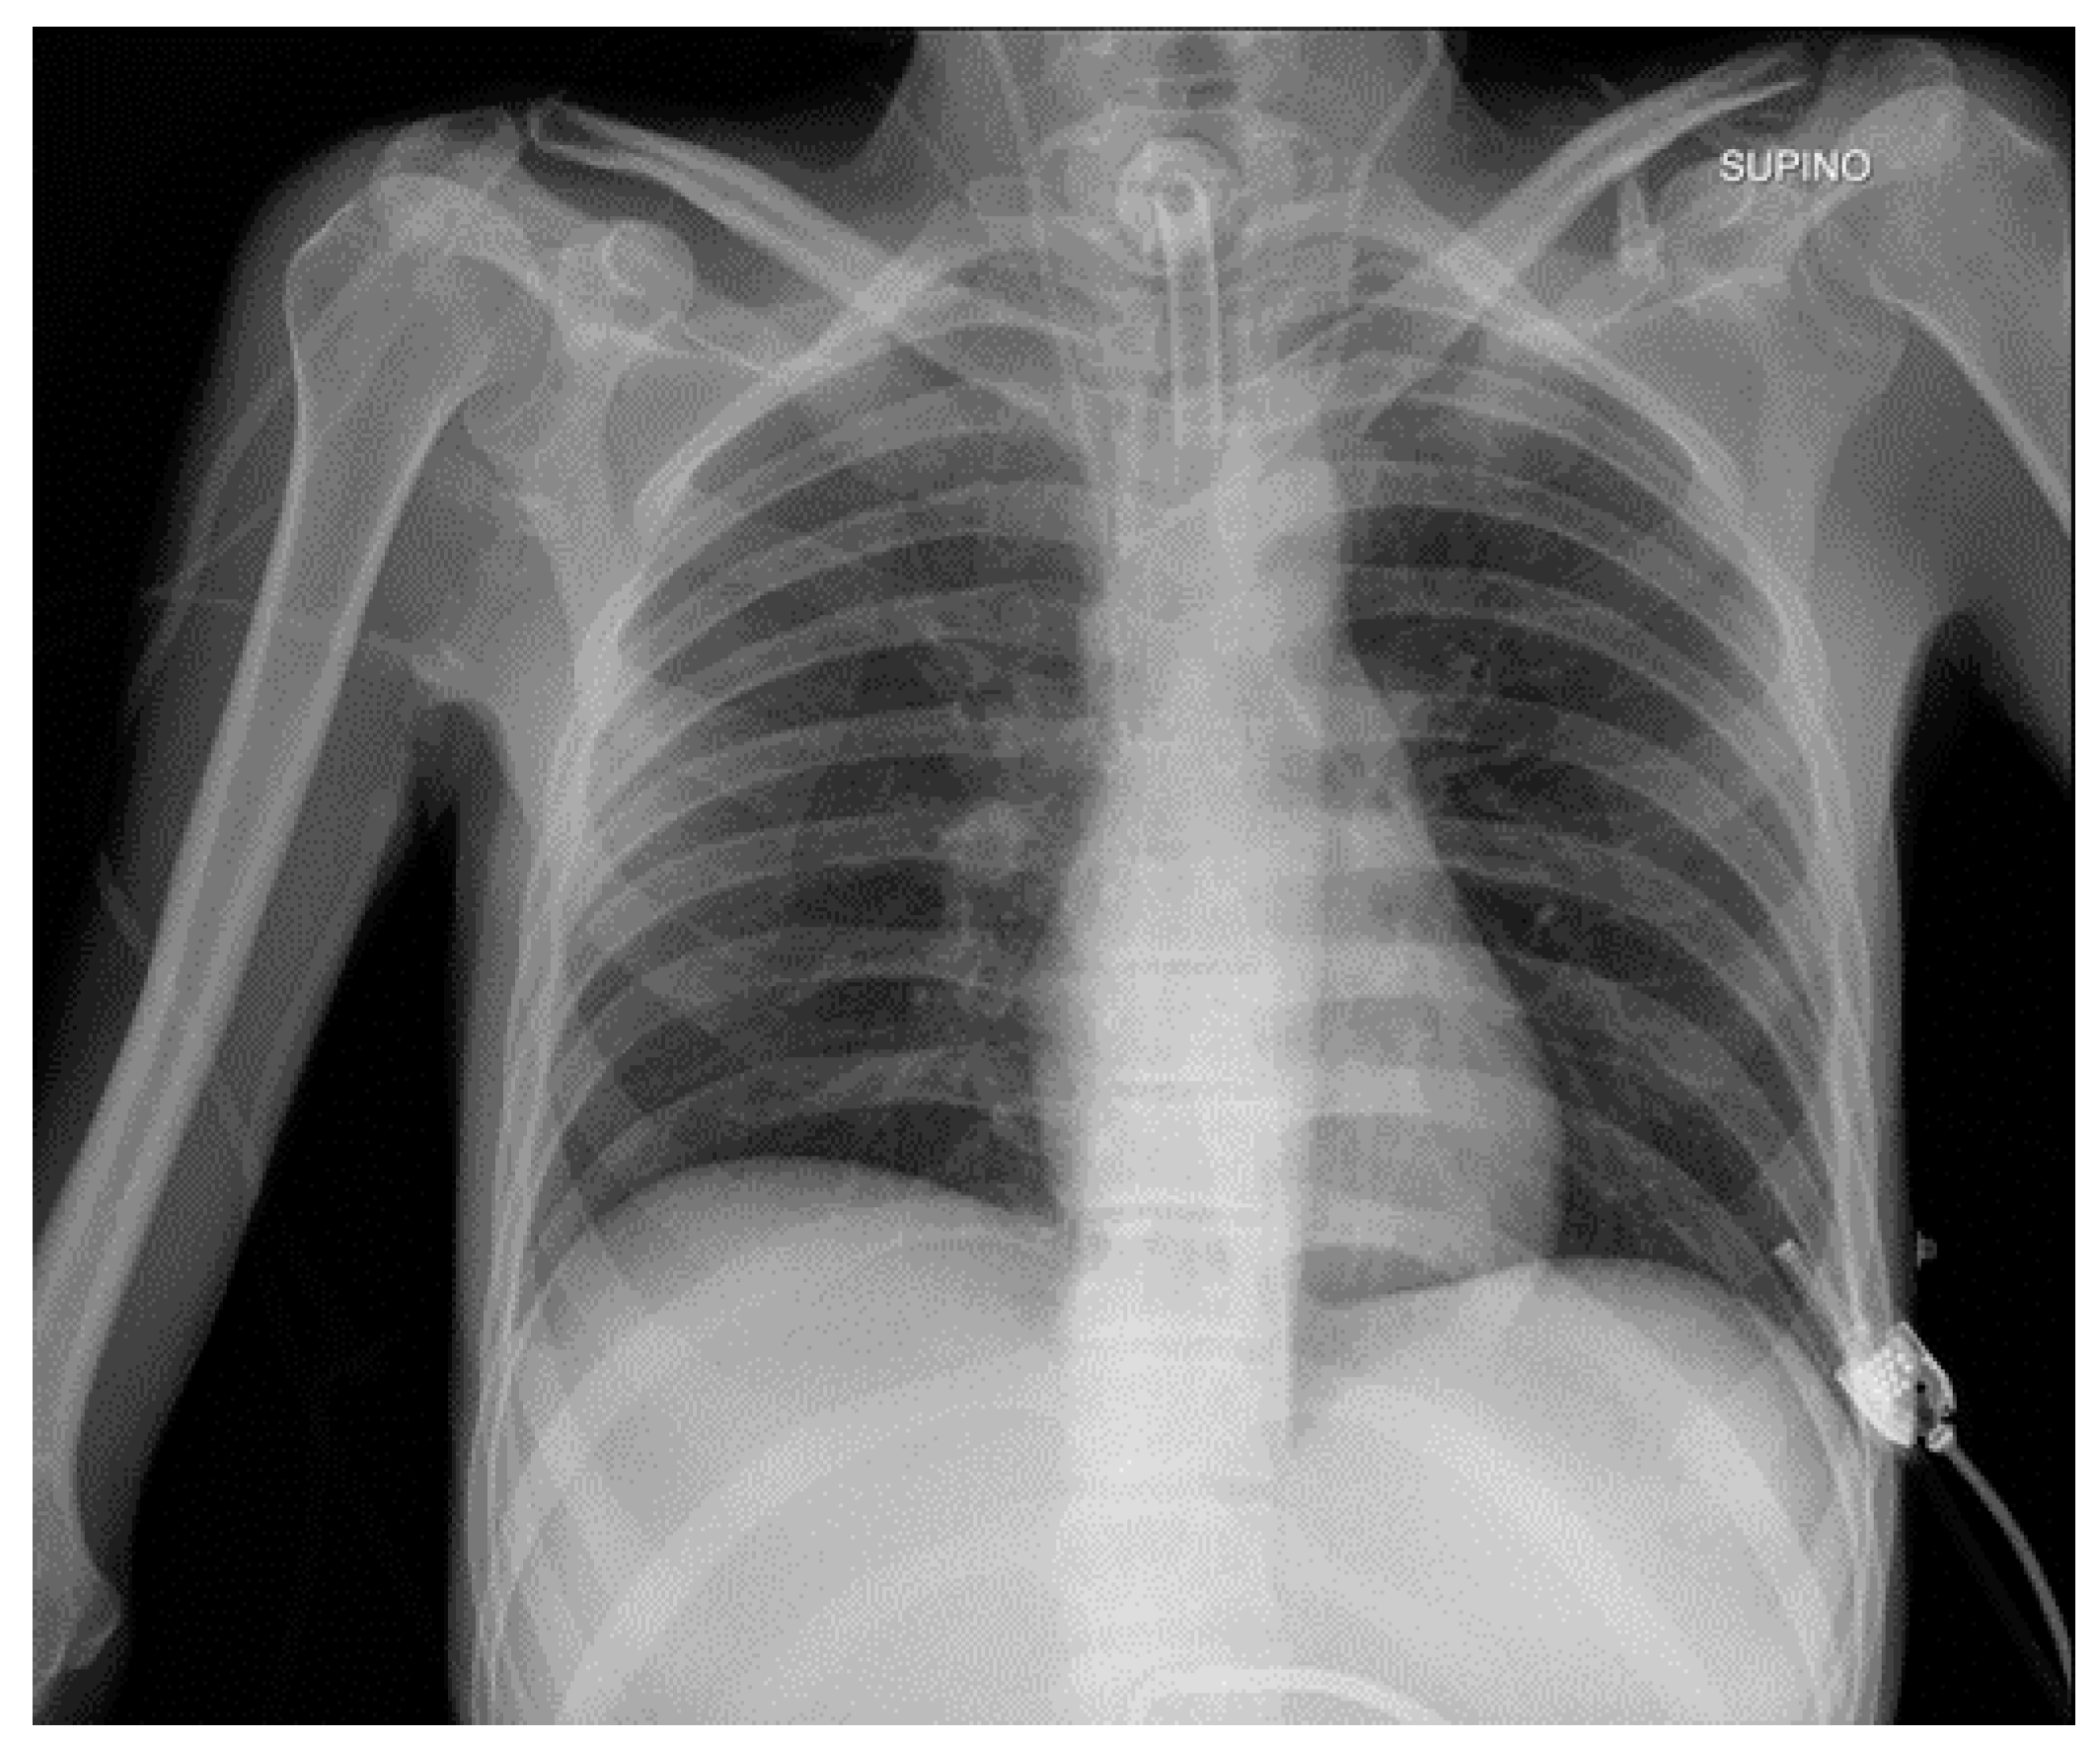

In image classification (e.g., identifying objects in medical scans), the features of similar images (such as pixel intensity or texture) naturally cluster together. A semi-supervised learning model can use the labeled examples to define these clusters, then assign pseudo-labels to the remaining data based on those patterns.